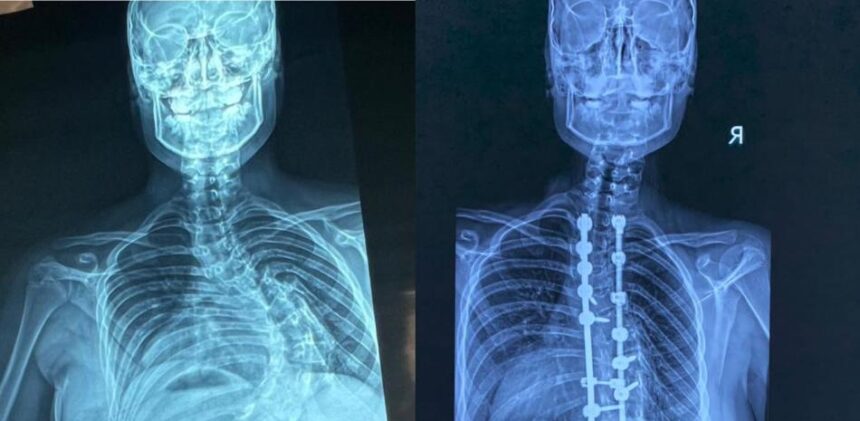

Unas 350 cirugías de corrección de deformidades de columna vertebral pediátrica se han realizado en República Dominicana, en los últimos cuatro años, en el hospital Robert Reid Cabral y la Sociedad Dominicana de Rehabilitación, coordinadas por el doctor Carlos Rodríguez Estévez, presidente de la Sociedad Dominicana de Cirugía de Columna.

En el Hospital Infantil Robert Reid Cabral se realizaron más de 250 procedimientos, mientras que 100 cirugías corresponden a la Sociedad Dominicana de Rehabilitación, cifra alcanzada en este año 2026.

En la unidad de escoliosis del Hospital Infantil Robert Reid Cabral se han realizado más de 250 cirugías de esta condición, una enfermedad que afecta a cientos de niños y adolescentes en el país.

El doctor Carlos Rodríguez explicó que, gracias al personal humano capacitado y a la tecnología disponible en ese centro de salud, pacientes de escasos recursos pueden optar por este procedimiento quirúrgico, cuyo costo ronda el millón de pesos y que no puede realizarse en cualquier institución.

La escoliosis es una desviación de la columna vertebral mayor de 15 grados. El especialista detalló que la forma más frecuente es la idiopática del adolescente.